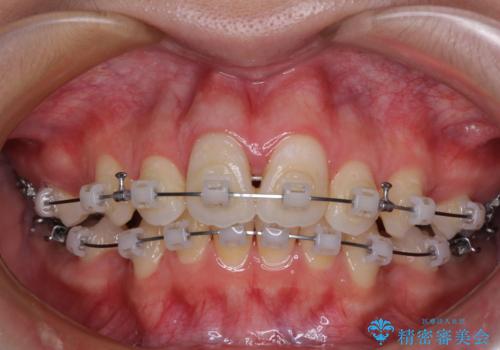

- クリアブラケット

- 1年9ヶ月

高校生ということもあり、治療期間は2年を切るスピードでした。